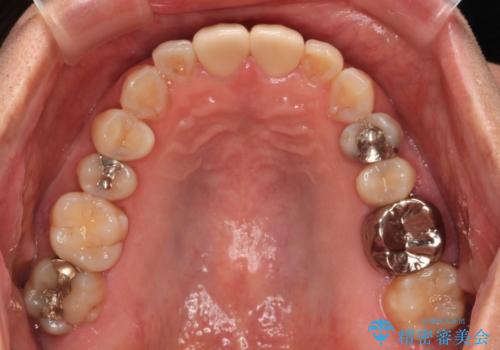

- つぎはぎのある前歯のセラミックの色合いが気になるとのことで来院された患者様です。

グレーの色が透けて見える気がする点が気になっていらっしゃり、やや黄色みのある色を希望されていました。

仮歯に置き換えた後にオールセラミッククラウンにて補綴治療を行うこととしました。